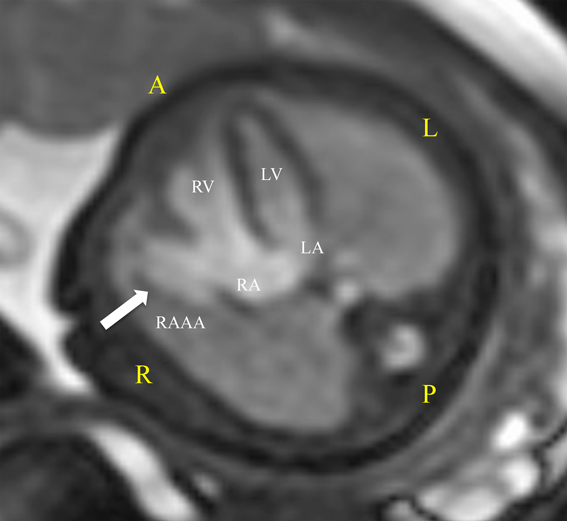

胎児期に診断し,無治療で経過観察できている先天性右心耳瘤の一例A Case of Congenital Right Atrial Appendage Aneurysm Diagnosed Prenatally and Followed-Up Without Treatment